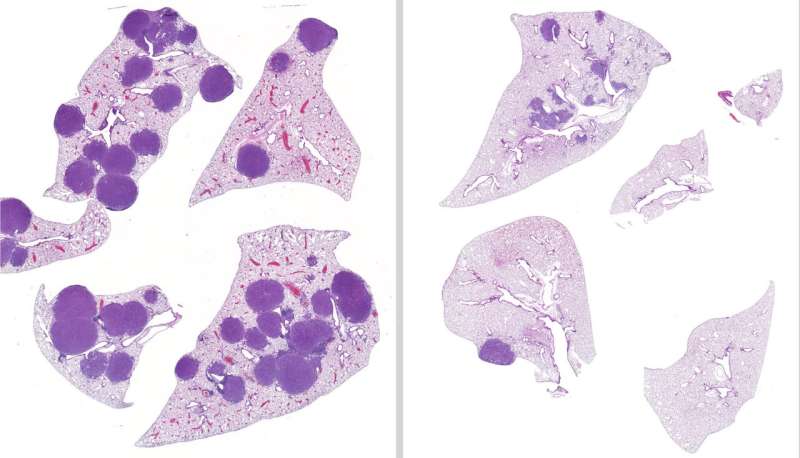

A new study led by Salk Institute Professor Reuben Shaw and former postdoctoral fellow Lillian Eichner, now an assistant professor at Northwestern University, revealed FDA-approved trametinib and entinostat (which is currently in clinical trials) can be given in tandem to produce fewer and smaller tumors in mice with LKB1-mutated NSCLC.

After treating mice with LKB1-mutated lung cancer with variable treatment regimens for 42 days, the team found that mice given both entinostat and trametinib had 79 percent less tumor volume and 63 percent fewer tumors in their lungs than the untreated mice. Additionally, the team confirmed that entinostat was a viable treatment option in cases where a tumor was resistant to trametinib.